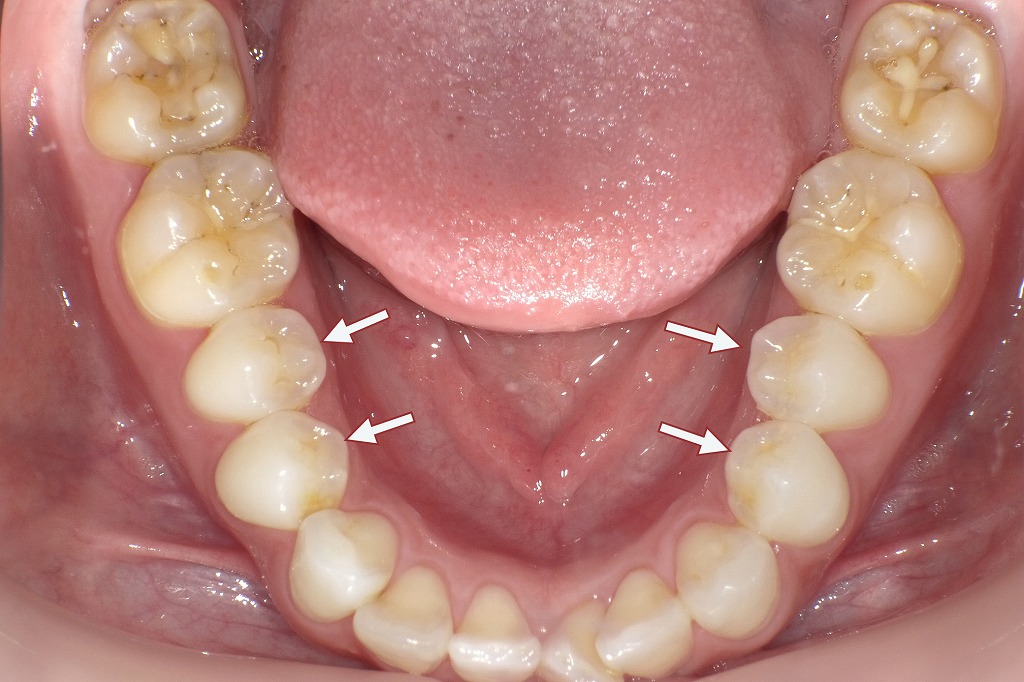

下記の口腔内写真は歯の萌出スペースが足りない、あるいは周囲の歯との位置関係が乱れている場合、小臼歯が本来の歯列から外れて生えてしまうことがあります。これが「頬側転移(きょうそくてんい)」や「舌側転移(ぜっそくてんい)」と呼ばれる現象です。